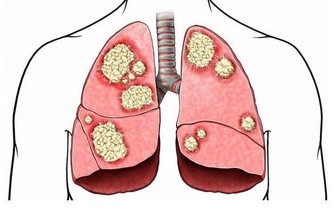

小編說: 明代李時珍在《本草綱目》記載:「艾灸百病、理氣血、逐寒濕、溫經止痛,以三年陳艾為勝」。這裡的「艾」說的就是艾草,大家都認識嗎? 假若說杏是中醫之花,那麼艾便是中醫之草了。艾草有調經止血、安胎止崩、散寒除濕之效。治月經不調、經痛腹痛、流產、子宮出血,根治風濕性關節炎、頭風、月內風等。現代實驗研究證明,艾草具有抗菌及抗病毒作用;平喘、鎮咳及祛痰作用;止血及抗凝血作用;鎮靜及抗過敏作用;護肝利膽作用等,可謂是「萬用之草」。 艾草的功效 艾草性味苦、辛、溫,入脾、肝、腎。全草入藥,有溫經、去濕、散寒、止血、消炎、平喘、止咳、安胎、抗過敏等作用。